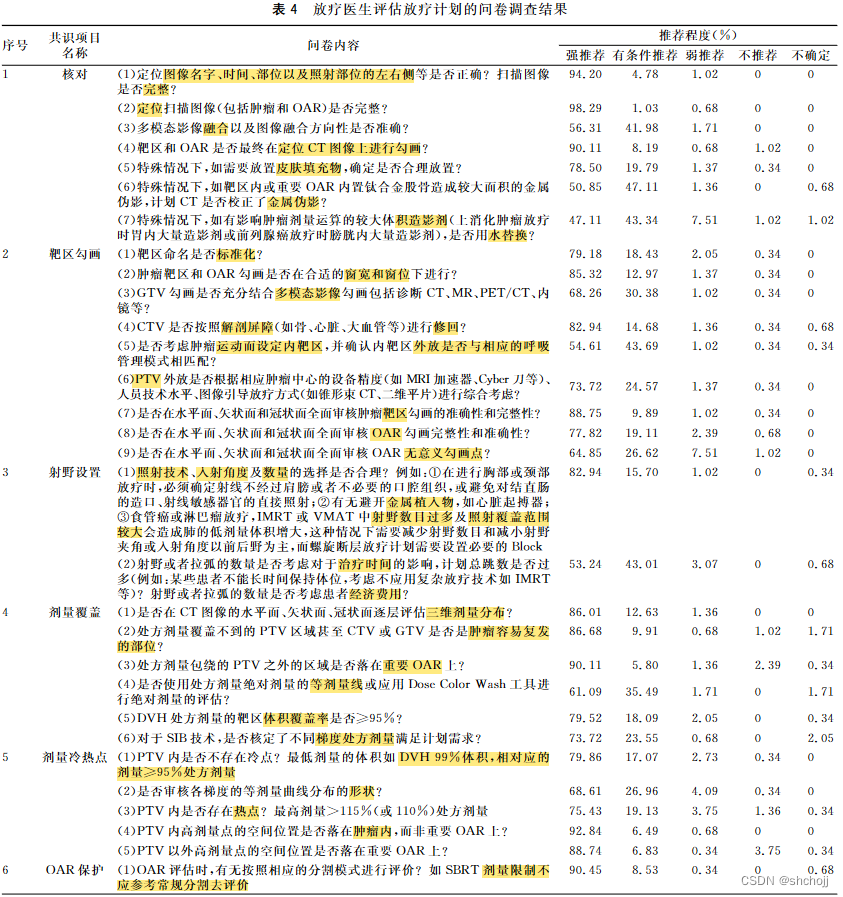

1、核对

2、勾画(Target&OAR)

3、射野(Beam)

4、剂量分布(DVH)

5、冷热点(cold&hot)

6、OAR保护

7、权衡取舍

8、处方剂量(RxDose)

9、确认